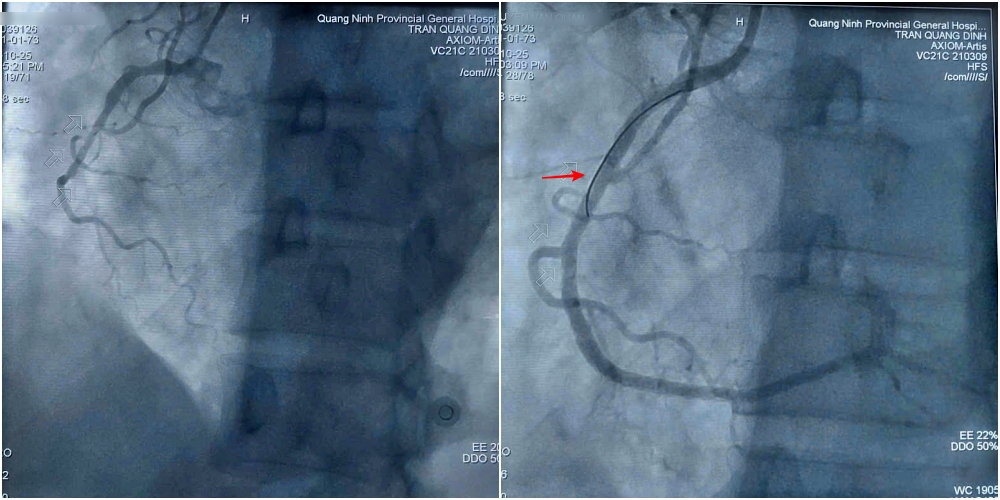

Hình ảnh trước và sau can thiệp đặt stent tái thông mạch vành cho bệnh nhân.

Sau khi hội chẩn và giải thích rõ tình trạng cho gia đình, ca bệnh được đội ngũ bác sĩ khoa Phẫu thuật và Can thiệp Tim mạch tiến hành khẩn trương. Kết quả chụp mạch cho thấy tổn thương nặng 3 thân động mạch vành, trong đó hẹp tắc hoàn toàn động mạch vành phải.

Kíp can thiệp tiến hành nong bóng và đặt 2 stent để tái thông động mạch bị hẹp tắc. Hình ảnh chụp kiểm tra sau thủ thuật cho thấy stent thông tốt, dẫn máu trở lại nuôi tim.